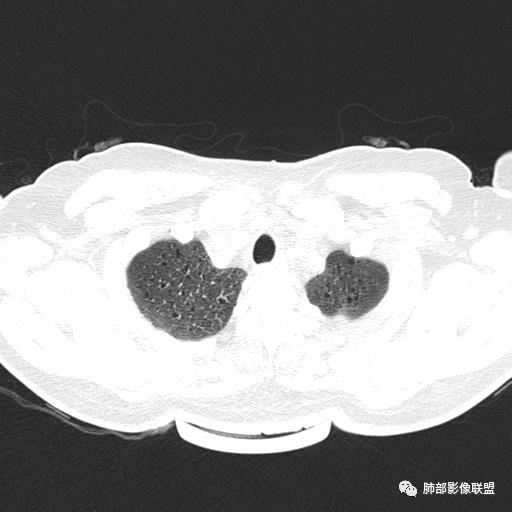

CT表现:双肺弥漫大小不等的薄壁囊腔,囊壁<2mm,外形规则,血管影多位于囊腔周围,囊腔之间肺组织正常,随着疾病进展到晚期,囊腔变大、增多,不可胜数,囊腔可融合成较大的囊,与肺气肿相似,形成间质性肺纤维化。部分病例可出现结节影。

中年女性,不吸烟

双肺弥漫囊腔,累及肋膈角,囊腔形态相对规则单一。